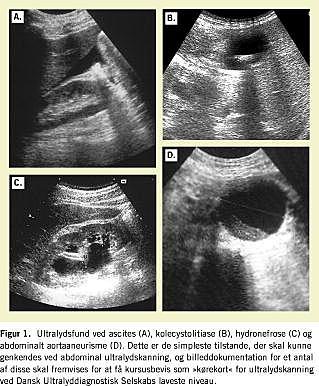

Denne udbredelse af ultralyddiagnostik til nye specialer foregår parallelt verden over, men i modsætning til i mange andre lande, f.eks. USA, har der traditionelt aldrig i Danmark eksisteret en egentlig konkurrencesituation mellem de etablerede ultralyddiagnostikere og »de nye«. Tværtimod, Dansk Ultralyddiagnostisk Selskab (DUDS) har siden stiftelsen i 1974 på eksemplarisk vis levet op til sin bredt formulerede formålsparagraf »at befordre teoretiske og praktiske fremskridt på det ultralyddiagnostiske område«, ved årlig afholdelse af et stigende antal almene kurser, og de enkelte medlemmer har landet over indgået i utallige projekter med kliniske specialer. DUDS blev dannet som et multidisciplinært selskab med urologen, professor Hans Henrik Holm i spidsen for en femmandsbestyrelse, der yderligere bestod af to gynækologer, en ingeniør og en sygeplejerske, og DUDS fremstår med sine mere end 700 medlemmer fordelt på adskillige specialer i høj grad fortsat som et multidisciplinært forum for udvikling af ultralyddiagnostik. DUDS fungerer i henhold til lægelovens § 14 som sagkyndig vurderingsinstans ved besættelse af ledende lægestillinger inden for medicinsk ultralyddiagnostik og er derfor forpligtet til at være på forkant med fagets udvikling inklusive have det nødvendige udbud af kurser og etablering af eventuelle standarder. DUDS er medlem af den europæiske sammenslutning af ultralydselskaber (EFSUMB) og følger deres retningslinjer vedrørende uddannelse i ultralyddiagnostik, som de er beskrevet i dokumentet Minimum training requirement for the practice of medical ultrasound in Europe i 2003. Heri defineres der tre niveauer af ekspertise i ultralyddiagnostik, hvoraf læger, der foretager selvstændige ultralydskanninger, som minimum skal kvalificere sig til niveau 1. Der foreligger ikke i skrivende stund en egentlig sanktionering af dokumentet fra sundhedsmyndighedernes side, men EFSUMB står med sine mere end 18.000 medlemmer i ryggen stærkt, den dag dette kommer på tale, og dokumentet hviler herudover på principperne i en betænkning udgivet af WHO om samme emne. DUDS's kursusudvalg har påbegyndt et større planlægningsarbejde med at definere de eksisterende kurser i forhold til de ovennævnte retningslinjer og udbygge kursusudbuddet, så det matcher både de nuværende (Figur 1 ) og de snarligt kommende uddannelseskrav. Arbejdet er godt i gang, men er også omfattende og kan kun gennemføres ved samarbejde med de specialeselskaber, som forventer eller ønsker ultralyddiagnostik implementeret i deres fag. Vi har i øjeblikket et samarbejde med bl.a. Dansk Radiologisk Selskab, Dansk Kirurgisk Selskab, Danske Kirurgers Organisation og Dansk Reumatologisk Selskab, men vi vil gerne opfordre andre til at henvende sig, hvis de imødeser et behov for uddannelse i ultralydskanning. Det samlede nuværende kursustilbud kan ses på DUDS's hjemmeside www.duds.dk